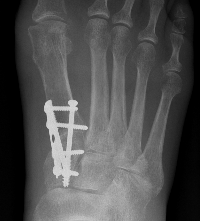

Arthrodesis

Indications

- hallux valgus with arthritis

- severe hallux valgus

- neuromuscular disease i.e. cerebral palsy

- rheumatoid arthritis

- salvage procedure for failed procedures

Technique

Approach

- dorsal approach

- medial approach

Position

- 10 - 15° valgus

- 10- 15° dorsiflexion relative to plantar surface / 20 - 25° relative to metatarsal shaft

Fixation

- screws / plate / screws + plate